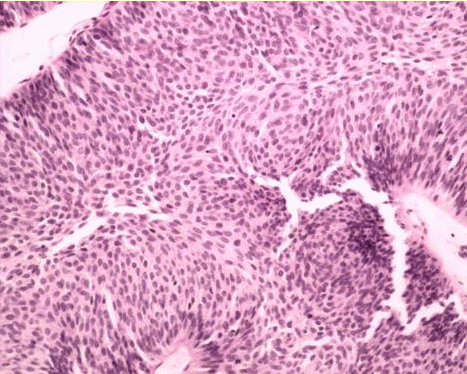

尖锐湿疣青壮年男性患者居多,主要表现在外生殖器部位,和肛周部位出现

尖锐湿疣,是由人乳头瘤病毒(hpv)感染导致的一种性传播疾病.